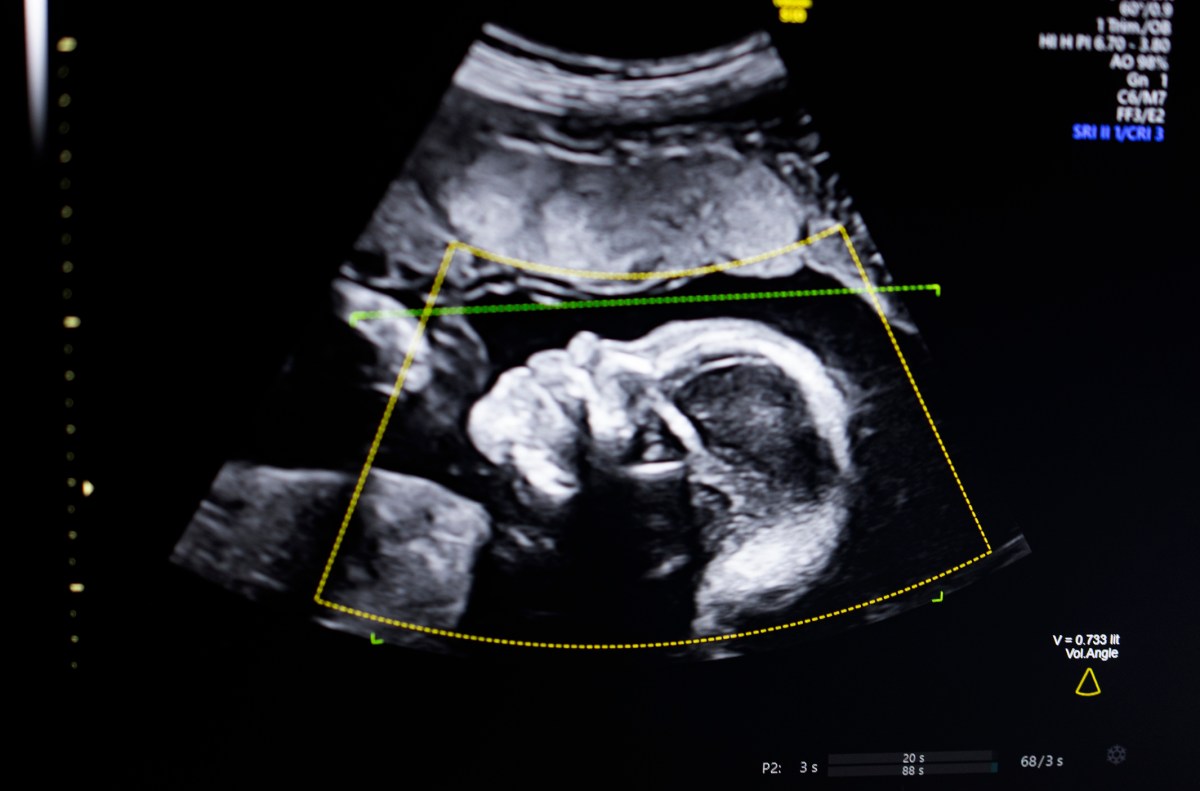

A tecnologia usa IA de visão computacional “para apoiar a avaliação da qualidade do ultrassom fetal, integridade anatômica, relatórios automatizados e integração perfeita em fluxos de trabalho clínicos”, disse Bustami ao TechCrunch.

Bustami disse que a ultrassonografia pré-natal se tornou a “pedra angular” do monitoramento da gravidez, mas suas imagens de baixa qualidade podem levar a erros de diagnóstico.

Bustami disse que a parte mais difícil não foi construir seus modelos de IA, que foram treinados em um conjunto diversificado de 11.000 ultrassons, mas garantir que a tecnologia funcionasse de maneira confiável no mundo real, especialmente em dados demográficos com maior risco de um resultado trágico.